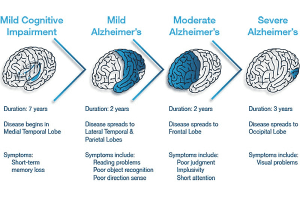

مراحل پیشرفت بیماری آلزایمر

مراحل پیشرفت بیماری آلزایمر